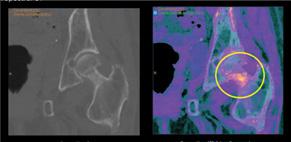

software IA asistă radiologul în interpretarea IRM de prostată prin realizarea volumetriei prostatice și prin detectarea ariilor suspecte, cuantificarea lor conform scorului PI-RADS, îmbunătățind acuratețea evaluării cancerelor de prostată, precum și cartografierea acestora pentru o mai buna comunicare cu urologii. <figura 7>